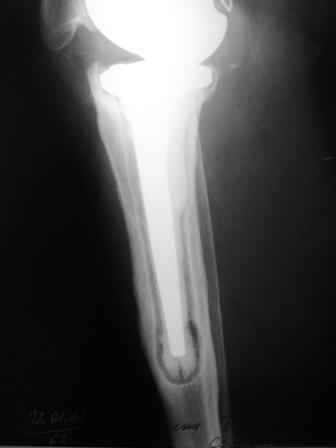

Уважаемые коллеги!Хотелось бы услышать Ваше мнение о возможности и способе помощи больной. 1939 г.р. В 1995г. эндопротезирование правого коленного сустава протезом Феникс, в 1999г. в г. Томске - ревизия - ротационный хинч W.Link. C 2005г. прогрессирует варусная деформация за счетнестабильности тибиального компонента. Попытка ортезирования - без эффекта. Попытка направить в ФСМУ без эффекта, да и больная не хочет никуда ехать.С уважением, Leonid

Уважаемый Михаил! Спасибо за ответ. К сожалению, бабка не соглашается на артродез - хочет сохранить колено. Я думаю о возможности ревизии тем же протезом - бедро оставить, голень удлинить полым гвоздем на весь диафиз и посадить на цемент?

Технически можно надеть гвоздь на ножку протеза

Понятно что для решения на операцию артродеза необходимы веские причины. Но я не уверен что здесь асептическое расшатывание. Судя по снимкам, бедренный компонент стоит не плохо, и есть рассасывание костной ткани вокруг всего протеза в голени. Что-то мне подсказывает об инфекционном процессе, возможно вялотекущем. В наших условиях я сделал бы обследование включающее анализы крови с СОЭ, СРБ. Сделал бы пункцию коленного сустава или даже биопсию мягких тканей для посева и микроскопии.